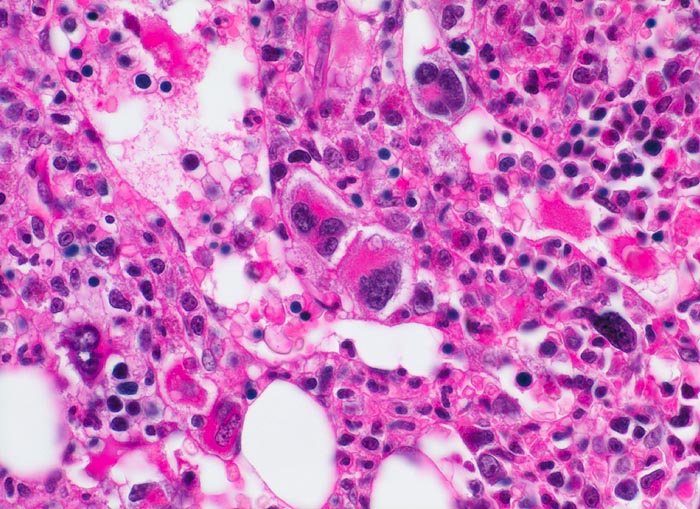

Primäre Myelofibrose (PMF)

Knochenmark, Beckenkamm

Neben atypischen, teils nacktkernigen Megakaryozyten zahlreiche Erythropoeseherde und myeloische Zellen verschiedener Reifungsstufen. Die Hämopoese ist auch in den dilatierten Markgefässen nachweisbar.

Splenomegalie, leichte Anämie, Leukozytose und Thrombozytose festgestellt bei einer Routineuntersuchung bei asymptomatischer Patientin.

Histologie

400